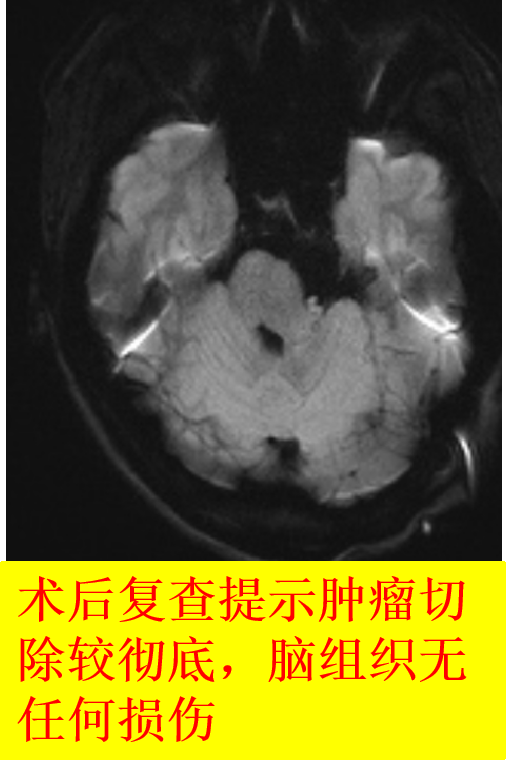

术前磁共振弥散

术后磁共振弥散示肿瘤切除较完全